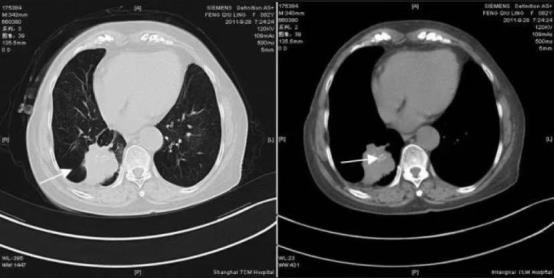

1)直接征象:CT可清楚显示增厚的支气管管壁,管腔的偏心性狭窄及软组织肿块。肿块呈类球形,中央型肺癌肿块靠近肺门,周围型相对远离肺门。密度多均匀,钙化少见,常呈砂砾状。肿块较小时其内可见未被瘤细胞占据的支气管或肺泡,表现为小泡状或小条状透亮影,称为空泡征或充气支气管征。肿块较大时可形成偏心性厚壁空洞,内壁可见壁结节,常无液平。肿瘤可表现分叶状,即分叶征,轮廓凹凸不平,其中深分叶征在肺癌诊断中有较大价值。肿瘤还可表现为毛刺征,即边缘呈放射状细短或粗长毛刺,自肿瘤边缘向周围延伸。而周围血管向肿瘤部位集中并在瘤灶处中断或贯穿瘤体的血管集束征大多出现在周围型肺癌。

肺窗示右下肺肿块边缘有分叶、毛刺征象,纵膈窗示肿块内砂砾状、簇状钙化